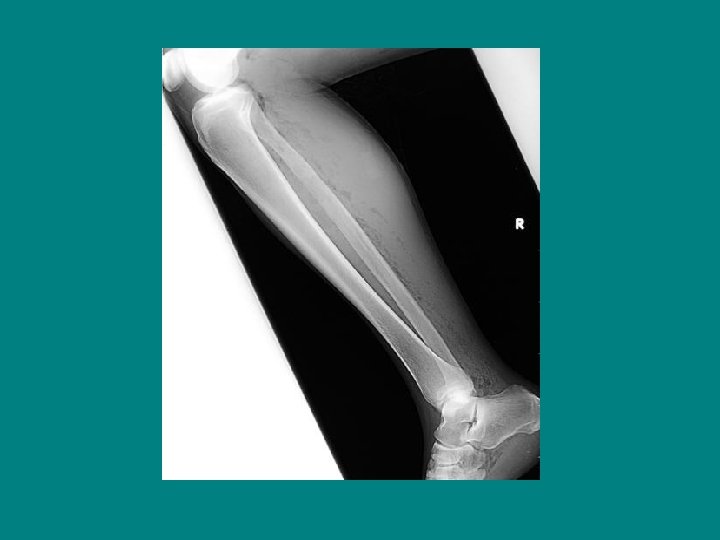

Radiographic Testing ü Plain x-ray: poor screening test. ü CT scan: more sensitive (plain) inflammatory changes gas formation fascial thickening: 80% sensitivity ü MRI: sensitivity 90 -100%, specificity 50 -85% prohibitive in critically ill, or unstable patients. (contrast-enhanced study)

Necrotizing fasciitis with gas forming organisms